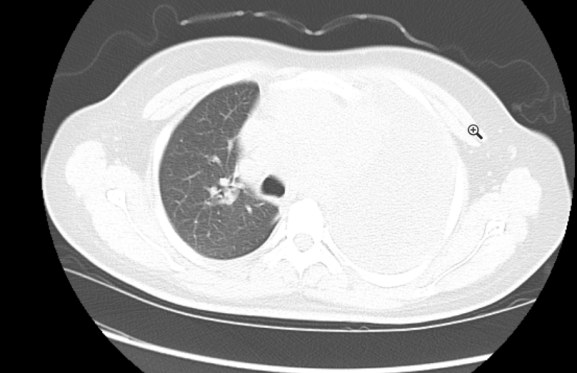

2021-03-13 我院心脏超声示心包积液。胸部超声示双侧胸腔积液。腹部超声示腹腔未见明显积液。胸部平扫(CT)提示前纵隔占位性病变,左侧心膈角区淋巴结;左侧大量胸腔积液,右侧少量胸腔积液,左肺局部膨胀不全,右肺中叶小结节,纵隔略右偏,心包大量积液。

2、纵隔肿物

患者经过穿刺引流后氧合明显改善,鼻导管吸氧下呼吸氧合可,血流动力学基本稳定,转普通病房治疗。同时复查了肺部CT。

患者存在纵隔肿块,经过同意后予超声引导下行肿块穿刺活检。病理结果提示:恶性淋巴瘤。后期血液肿瘤科进行了专科治疗。